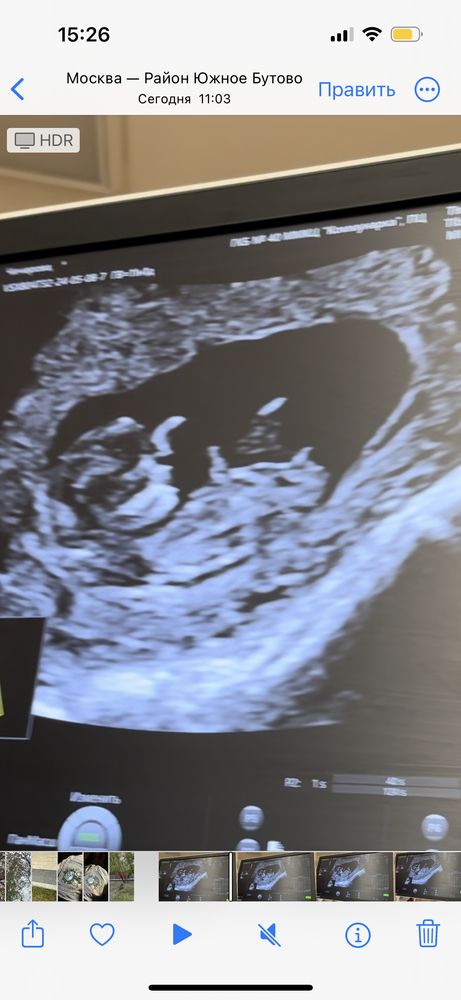

Первый скрининг. Мальчик или девочка? Кто нибудь умеет определять ?

Девочка похоже

01.06.2024

Девочка.

а врач что без опыта попалась? на девочку похоже

Мальчик, если это не пуповина ☺️🐣

Мальчик

А какой срок

Aisha, 11 недель